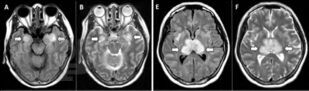

Пособие подготовлено в соответствии с требованиями ФГОС ВО по специальности 31.05.01 Лечебное дело, действующего учебного плана и рабочей программы (2020 г.) для изучения дисциплины «Неврология, нейрохирургия». В нем излагаются современные представления об этиопатогенезе новой коронавирусной инфекции COVID-19, подходы к ее диагностике и лечению, а также клинические особенности поражения нервной системы.

Отдельно рассмотрена организация медицинской помощи пациентам неврологического профиля в условиях распространения COVID-19. Уровень изложения материала соответствует современным требованиям и позволяет оптимизировать организацию и управление самостоятельной работой обучающихся. Пособие содержит тестовые задания и ситуационные задачи, которые помогут в изучении неврологической аспектов COVID-19.